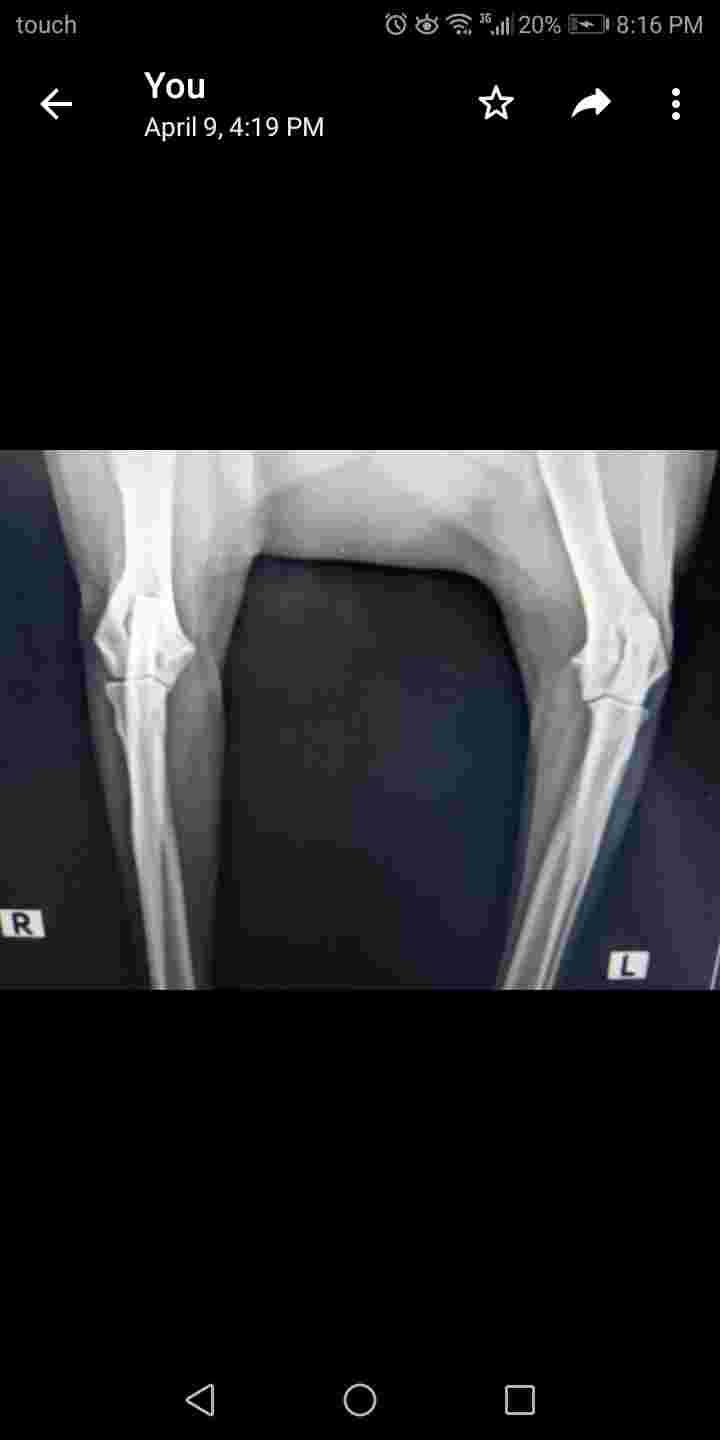

Hi Dr. Can you please check xray of my femele 10yrs golden. She is on glucosamine since a year now she sometimes limps the vet said it's not dangerous but he didn't explain to me what should I give her supplements more or if the xray is not bad can you give me info I care for her health at this age.

Unfortunately its very hard to interpret pictures of X-rays that have been uploaded; detail and subtle changes are difficult to appreciate. Having said that, I don't see anything in these X-rays that is terribly concerning to me. It may be that she does have some arthritis pain causing her occasional limp. Glucosamine supplements can be helpful. Cosequin is a great one , so is Glycoflex. Physical therapy offered by a canine rehabilitation professional can be helpful for older dogs in terms of maintaining comfort, health, and mobility. Find someone here: https://www.rehabvets.org/directory.lasso Acupuncture can also be really helpful for these guys. Ask your vet if they do acupuncture, or if they recommend anyone in particular. If not, find a veterinary acupuncturist here: https://curacore.org/find-a-practitioner/ I hope that helps! Thanks for asking PetCoach!